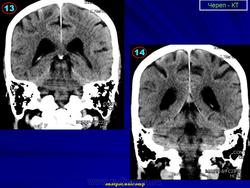

Нормальная КТ - анатомия головного мозга.

Продолжение.